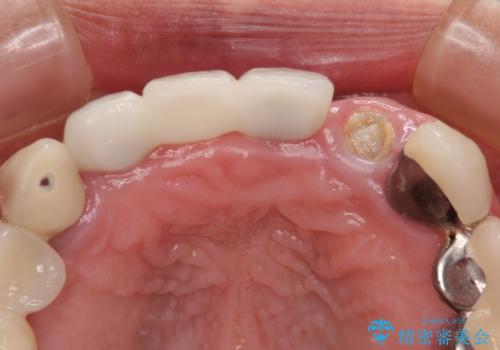

インプラントの安定度も高く、抜歯と埋入から2か月後にはオールセラミッククラウンを装着することができました。